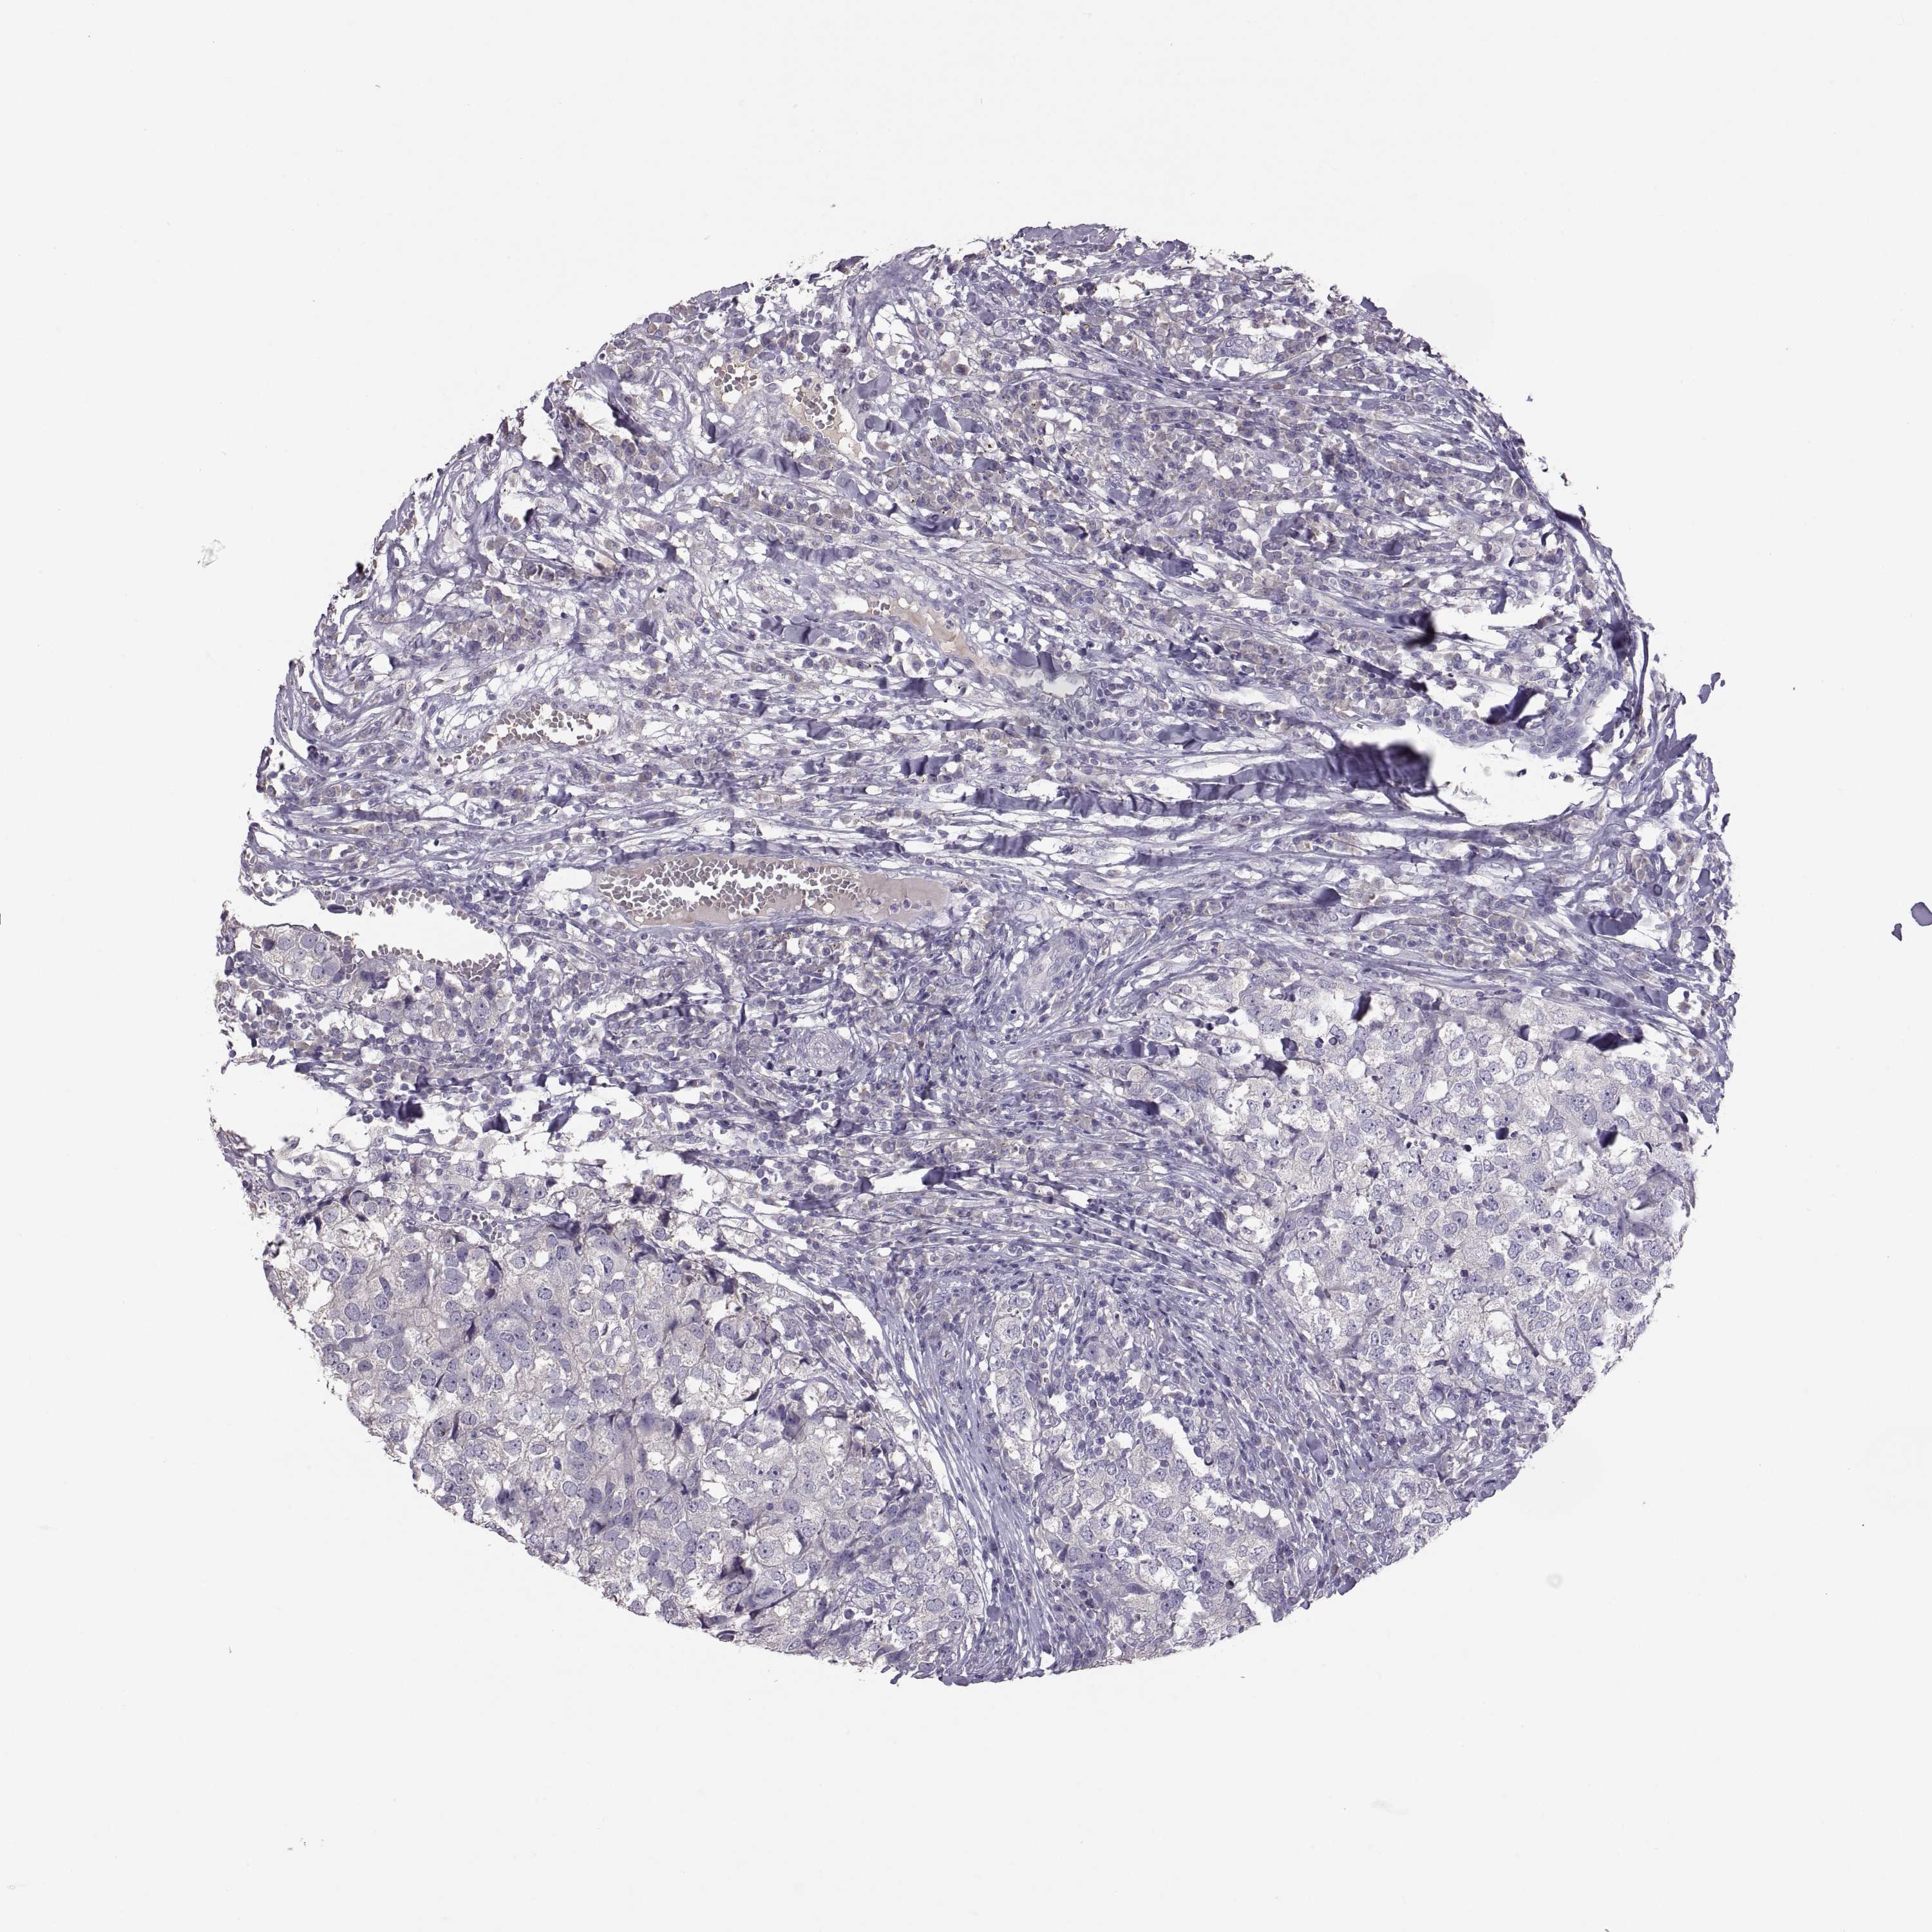

BRCA TCGA BRCA VALIDATION PROTEIN EXPRESSION

Breast cancer

Human cancer